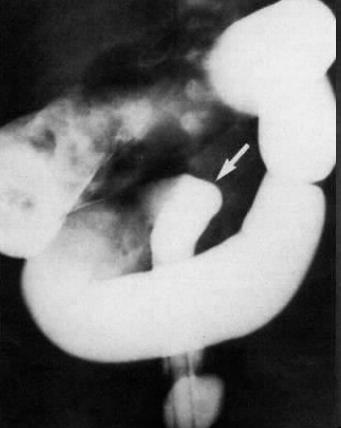

Aspect de

lavement baryte de meme cas : La portion recto-sigmoidienne

innertie ( fleche blanche ) se diminue sa diametre

et la colon ascendent et transverse sont dilate. |